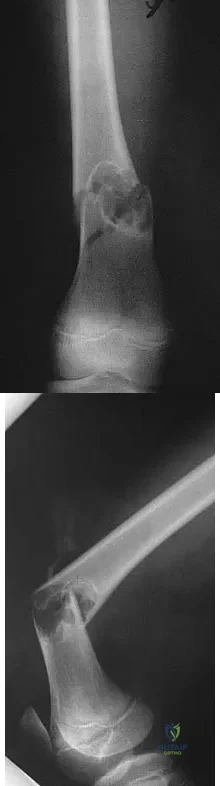

Question 33

Figure 31 shows the AP and lateral radiographs of the elbow of a 56-year-old man with chronic polyarticular rheumatoid arthritis. His function continues to be limited by pain with activities of daily living. Examination shows that his total arc of motion is 110 degrees. Nonsurgical management has failed to provide relief. Treatment should now consist of

Explanation